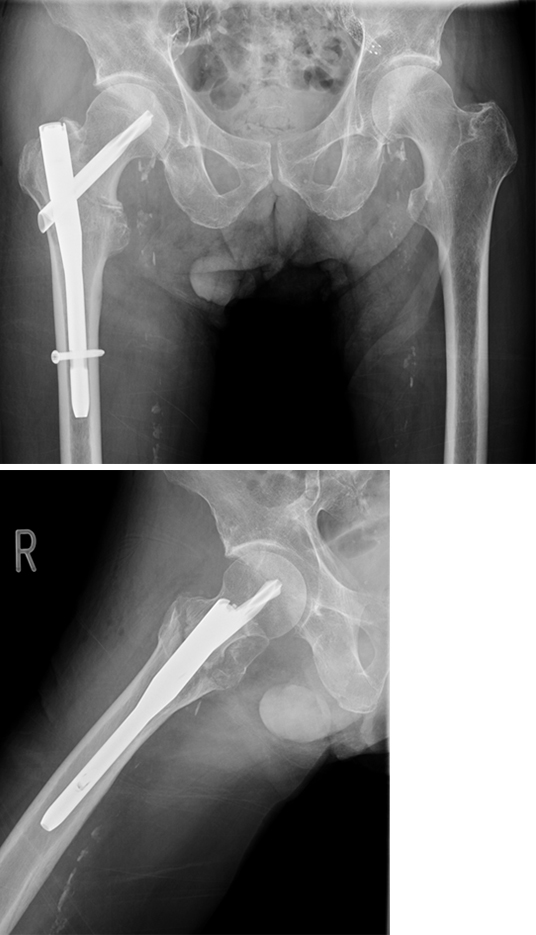

Case provided by Michael Blauth, Innsbruck, Austria

Case 1: Fall at home

An 83-year-old female patient sustained a 31-A.2.2 fracture of the right proximal femur after a fall at home (Figs 1-2). Intraoperative and postoperative images are shown (Figs 3-5).